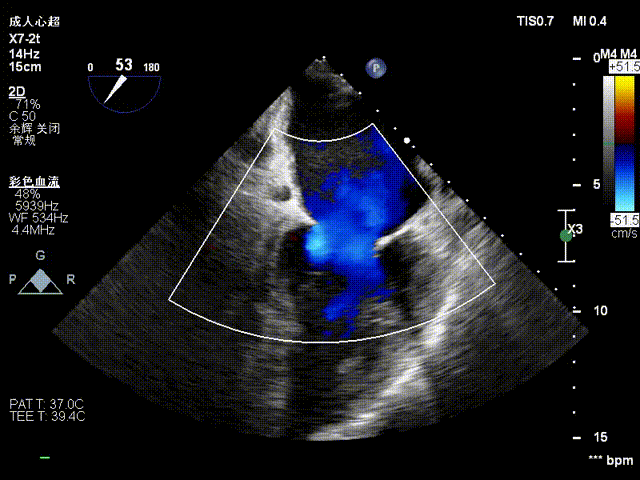

夹合后反流评估

检查示组织桥明显,夹合器稳定,残余反流明显减少,降低至1+等级,二尖瓣平均跨瓣压差为2mmHg,经团队评估,手术效果达既定预期,各项指标平稳,顺利结束手术。

术后压差评估